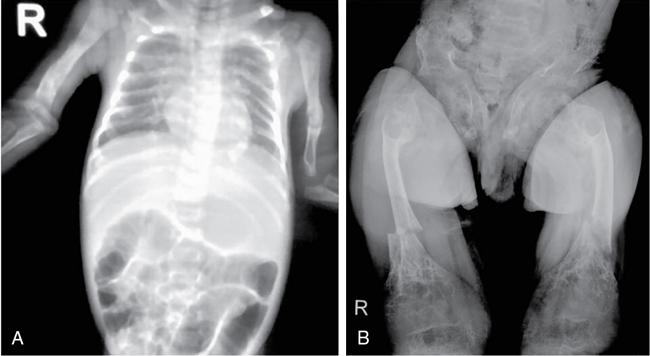

MISCELLANEOUS PAEDIATRIC RADIOGRAPHY – TECHNIQUES AND INTERPRETATION: SKELETAL SURVEY Padma V. Badhe The skeletal survey, generally performed in children, is a set of radiographs done in order to evaluate the entire skeleton. A skeletal survey, commonly used to evaluate skeletal dysplasias, acquired metabolic disorders and suspected child abuse, is still the key radiological investigation for the same. Hence, an explicit understanding of the technique along with the common disorders forms the basis of making a diagnosis in these paediatric pathologies. A skeletal survey is done for various skeletal dysplasias, non-accidental injury (battered baby syndrome) and suspected child abuse. It can also be done in cases of metabolic bone diseases, disseminated infections, multiple myeloma, eosinophilic granuloma. It is also used in evaluation of metastatic bone diseases and polyarticular arthropathy. Orthogonal views of the skull, spine, pelvis and one extremity are taken, preferable in standing position. For preterm babies/newborns, AP and lateral views of babygram may be taken. Projections: For skeletal dysplasias: Additional views: Both extremities may be taken if epiphyseal abnormalities and limb asymmetry is present. Focused views for specific pathologies may be taken. When a diagnosis remains uncertain, 1 year follow up is usually recommended. For preterm babies/newborns: AP and lateral views of babygram may be taken with additional specific views for extremities. For suspected non-accidental injury (NAI): AP and oblique view of chest is taken for better evaluation of the ribs. AP view of abdomen with pelvis. Both upper and lower limbs are evaluated. In lower limbs, two projections in AP and lateral (one with both femur including hip and knee joints; and another for foot and ankle) is taken. AP and lateral views of whole spine, skull. Oblique view of hands. A babygram should be avoided in cases of NAI, as subtle fractures are easily missed. Proper legal documentation while taking the views is very important and ideally two health care professionals must be present. For metabolic disorders: entire skeletal survey is usually not required. Specific views of hands, knees and spine may be taken with additional views depending on the suspected pathology. Centring point: Varies according to the part being examined. Angulation, collimation and orientation: Varies according to the part being examined. Images must be well collimated to obtain lower radiation dose. Detector size: Varies according to the part being examined: 8″ × 10″, 10″ × 12″, 11″ × 14″. Exposure: Ideally high kVp images are taken to reduce radiation dose. But in suspected NAI, low kVp/high mA images are recommended to better demonstrate findings. SID (Source Image Distance):100 cm Grid: Grids are not routinely used to image spine, pelvis, skull and abdomen in children. Radiation dosage: 0.3–3 mSv Essential image characteristics: Adequate spatial resolution, high signal to noise ratio, low kVp (50–70) for high contrast should be done. Excellent bone and soft tissue details are required. The presentation of skeletal dysplasia can range anywhere from minimal stunting of growth and bowing of limbs to severe dwarfism and multiple fractures. Knowledge of the commonly encountered dysplasias with an approach to arrive at a diagnosis is vital in any Radiologist’s practice The following flow chart summarizes the classification of important skeletal dysplasia: The following table summarizes the various dysplasias affecting the axial skeleton: TABLE 7.5.1.1 The following flow chart summarizes the working approach to skeletal dysplasias: Osteopetrosis (Albers-Schonberg disease/Marble bone disease) (Fig 7.5.1.1): Osteopetrosis clinically presents with anaemia/thrombocytopenia or cranial nerve compression. Radiological features include generalized increase in bone density with loss of medullary space. However, cortico-medullary appreciation with cortical thinning is also rarely seen. Bone within bone appearance with Erlenmeyer flask deformity is also noted. Pyknodysostosis (Figs. 7.5.1.2 and 7.5.1.3): patient presents with short stature. Unlike osteopetrosis, there is no anaemia. Radiographs show generalized increase in bone density with preserved medullary canal. There is mandibular hypoplasia with obtuse angle. Acro-osteolysis is also a feature. Dental caries with osteomyelitis of the jaw may be seen. Sclerosing dysplasia presenting as wavy undulating new bone formation. Usually monomelic, lower limb and along one side. The classic appearance is described as Dripping candle Wax sign. It is a Sclerosing dysplasia with radiological features of symmetric juxta-articular involvement in epimetaphyseal region. They are 1–10 mm in diameter and uniform in size. No metabolic activity is seen on bone scans. This skeletal dysplasia shows diffuse decrease in bone density with paper-thin cortex. Fractures heal in normal time but shows callus with poorly cellular matrix. Wormian bones and enlarged sinuses may be seen. Codfish vertebra (Biconcave vertebra) may be seen. Metaphyseal corner fractures are not seen in osteogenesis imperfecta that helps to differentiate it from battered baby syndrome. There are four types of OI out of which type one is most common (Figs. 7.5.1.6 and 7.5.1.7). The radiological features of MPS include Osteopenia and Universal platyspondyly. The intervertebral disc spaces are maintained. Proximal pointed metacarpals is an important radiological finding. Hurler’s syndrome show anteroinferior beaking with short and wide metacarpals. Varus deformity of humerus is characteristically seen in Hurler’s syndrome (Fig. 7.5.1.8). Mental retardation & corneal clouding is seen in Hurler’s syndrome whereas these Hunter’s disease has normal intelligence with no corneal clouding. Morquio’s syndrome shows central beaking (Fig 7.5.1.9). This skeletal dysplasia shows normal bone density with rhizomelic limb shortening and normal trunk. Narrowing of spinal canal is classically seen with decrease in the Interpedicular distance caudally. Other radiological features include trident hand (separation of middle & third fingers), Champagne glass pelvis (short, flat ilia and small sciatic notch), bullet nose vertebra and overexpansion of skull with narrow foramen magnum (Fig. 7.5.1.10). This skeletal dysplasia is characterized by normal bone density with dwarfism and normal craniofacial skeleton. The interpedicular distance is normal. There is severe platyspondyly with anterior tonguing (disappears at older age). Other radiological features include increased disc space, short stubby metacarpals, small irregular epiphysis and widened metaphysis. Anterior tonguing is a feature of Pseudoachondroplasia. This form of skeletal dysplasia involves the spine and epiphyses (Fig. 7.5.1.11). There is normal bone density with rhizomelia. Spine and Pelvis can be involved. Premature osteoarthritis can be seen. The other characteristic features include Platyspondyly and small irregular epiphysis. There are two forms Spondyloepiphyseal dysplasia Congenital and Spondyloepiphyseal dysplasia Tarda. Spondyloepiphyseal dysplasia Congenita is Autosomal dominant and shows pear-shaped vertebrae. Spondyloepiphyseal dysplasia Tarda is X Linked recessive with heaped up vertebrae. It has two forms. The first form is Conradi Hunermann syndrome which is autosomal dominant characterized by asymmetric limb shortening with metaphyseal flaring (Fig. 7.5.1.12). The Autosomal recessive form is Fatal in first few years. Rickets: Rickets refers to deficient mineralization of the growth plate in the paediatric population due to deficiency of vitamin D. In an immature skeleton, there is abnormal mineralization at the zone of provisional calcification in the metaphysis due to osteoid deposition resulting in widening of the growth plate. The features of rickets include fraying, splaying and cupping (Fig. 7.5.1.13). Fraying denotes indistinct margins of the metaphysis whereas splaying denotes widening of metaphyseal ends. Term ‘Cupping’ is used for increased concavity of the metaphysis. These findings are typically seen involving areas of active growth (e.g. distal femur and proximal tibia in the knee) Bowing is a result of associated osteomalacia leading to weakening of weight-bearing lower limb bones. Other bone deformities such as genu valga, genu varum, protrusio acetabuli can also be seen. The lower ribs may also be drawn inwards inferiorly by the attachment of the diaphragm this is called Harrison’s sulcus. Scurvy: Scurvy is a result of dietary deficiency of Vitamin C (ascorbic acid). The classic presentation is that of a patient with an increased bleeding tendency and osteopenia with poor wound healing. Features of scurvy include generalized osteopenia with cortical thinning termed as ‘pencil-point’ cortex. Other radiological findings include the periosteal reaction due to subperiosteal haemorrhage. Expansion of the costochondral junctions occurs forming scorbutic rosary. Bleeding into the joint spaces may result in hemarthrosis. Circular, opaque radiologic shadow surrounding epiphyseal centres of ossification may result from bleeding (Wimberger ring sign) (Fig. 7.5.1.14). Frankel line may be seen. It represents dense zone of provisional calcification. Lucent metaphyseal band is seen underlying Frankel line called as Trümmerfeld zone. Metaphyseal spurs may be seen that result in cupping of the metaphysis (Pelkin spur). Pelkin fracture (metaphyseal corner fracture) can also be seen. Images obtained must be of good resolution with adequate bone and soft tissue details. Additional views: They have already been described in positioning. CT Brain in can be done in cases of NAI to look for subdural hematomas. A skeletal survey is the first-line imaging modality for evaluation of skeletal dysplasia, nonaccidental injury and metabolic bone diseases. The skeletal survey must be tailored according to the respective indication. It helps to characterize syndromic patterns in skeletal dysplasias, with evaluation of complications. In cases of diagnostic dilemmas, additional focused view and occasionally yearly follow-up is recommended. A high index of suspicion is needed in utilizing skeletal survey as a diagnostic modality in NAI. At the same time, one must also remember the legal and social implications of making this diagnosis. BABYGRAM Babygram is a colloquial term used for a radiograph of the whole body of a newborn or just the chest and abdomen (thoracoabdominal babygram) on a single image. As the name suggests it is a rather non-targeted study. It is most commonly requested after line placement. Evaluation of skeletal abnormalities in a deceased foetus is typically performed using anteroposterior and lateral views of a babygram. It helps in pointing out skeletal causes of death in stillborn or dead foetuses. This will help the treating physician and parents understand the reason for baby’s death. This will also help in future genetic counselling of the couple. Sometimes chest or abdominal radiographs of the baby are requested but due to radiographers error or inexperience with small babies, there is inclusion of the region not to be assessed leading to a false babygram. Babygram is most frequently done after line placement in neonates, to view the position of the umbilical vein or artery catheter and to confirm appropriate placement. It is a useful modality in skeletal dysplasias (Fig. 7.5.1.15) like osteogenesis imperfecta, thanatophoric dysplasia and chondrodysplasia punctata. It can also be used for skeletal deformations probably caused by foetus akinesia and in cases of Caudal regression syndrome. In stillborn foetuses, it is used for evaluation of skeletal dysplasias prior to an autopsy (Fig. 7.5.1.16). It is also used in screening for surfactant deficiency and in cases of Necrotizing Enterocolitis in preterm babies where it can help to see the bowel dilatation, intramural and portal venous gas. It can be done in aneuploidies like trisomy 18 and in cases of sudden infantile death syndrome. All the essential equipment and room need to be prepared including the exposure factor. This should be done prior to placing the baby on the table to prevent any neonatal heat loss. Ensure that the baby is correctly identified. Give brief explanation to the patient’s parents regarding the procedure, its risks and benefits. Ensure that the accompanying relative is not pregnant (if female). Parents/guardians/nurses should be instructed to hold the baby with arms above the head and legs straight down. Sandbags/tapes can be used to immobilize the baby. Avoid taking the radiograph when baby is crying. Normal appearance: The endotracheal tube should lie in the lower third of trachea, distance can vary with position of baby’s head. Umbilical artery catheter has an inferior dip along the internal iliac artery, which then turns superiorly along the aorta. The tip should lie in the mid-thoracic aorta (T6–T10) or lower (L3–L4) away from aortic branches to prevent any thrombosis. Umbilical venous catheter does not have the inferior curvature, but rather a posterolateral angulation to the right near the liver through the ductus venosus. The tip should lie in the superior IVC or right atrium at T8/T9 vertebral level (Fig. 7.5.1.17). Portal venous gas may be seen initially after insertion. In a stillborn foetus, the approximate gestation age of the foetus and corresponding ossification centres must be known. In early gestation, the lack of appearance of an ossification centre may be mistaken for skeletal dysplasia. Both chest and abdomen should be included. In a rotated patient, the distance between the spinous process to medial end of clavicles will be asymmetric. The medial end of clavicle should overlap the lung apex, if above, suggests lordotic image. Motion artefacts to be reduced as much as possible. A crying neonate may result in an expiratory film, and hence must be evaluated accordingly. In evaluation of skeletal dysplasias in the newborn, additional views of skull and hand have to be obtained. Baby gram is a useful diagnostic investigation for position of the paediatric umbilical catheters. It helps in general survey in skeletal dysplasia (Fig. 7.5.1.18). It is a simple, effective study in deceased foetus for diagnosis and further counselling, sometimes obviating the need for an autopsy. As baby gram is a non-targeted study, it increases the dose of radiation for the baby. As the exposure settings remain same for the entire body of the baby, the quality of the image decreases. This increases the chances of missing subtle findings. The babygram in a neonate is currently used to localize umbilical catheters. In stillborn fetuses, it is still an important study for documenting and confirming skeletal dysplasias. Understanding the normal appearance as per gestation age and patterns of various common skeletal dysplasias is essential for evaluation. Being a non-targeted study, it should not be used as an alternative study to evaluate the chest or abdomen considering radiation exposure and poorer image quality. INVERTOGRAM Invertogram was first described by Wangensteen and Rice in 1930. It was used as a first investigation to be ordered in evaluation of infants with clinically diagnosed or suspected Anorectal Malformation (ARM). ARM is a serious but surgically treatable congenital malformation with approximate incidence of 1 in 5000 live births. Though the diagnosis of this condition is based on clinical history and physical examination, imaging plays an important role in deciding the type of ARM, and associated complications to aid in management. International classification of anorectal malformations is as follows. Syndromic association is seen as a part of VACTERL defects, trisomy 21 13 and 18, Klippel Feil syndrome, cat eye syndrome etc. The main indication of Invertogram is to evaluate anorectal malformation in a neonate. A radio-opaque marker is placed over the external anal opening. Infant is held inverted by holding both thighs, maintaining this posture for at least 5 minutes before taking an X-ray in true lateral position (Fig. 7.5.1.19). Exposure is made during inspiration. The Invertogram should ideally be done 24 hours after birth as, the rectal gas may not reach the terminal segment if study is done too early. Pubo-coccygeal line (PCL) is drawn from upper border of pubic symphysis (which corresponds to centre of pubic bone on lateral X-ray) to sacrococcygeal junction. I point is the inferior most point of ischial ossification centre. A line which is drawn parallel to PC line passing through the I point is called I line. ‘A’ point is represented by marker placed at anal pit. The position of rectal pouch gas shadow is observed with respect to these lines and appropriate diagnosis is made (Fig. 7.5.1.21). A diagnosis of high ARM is made when gas shadow of rectal pouch is cranial to PCL. If rectal pouch gas shadow is in between PCL and I line, it is called as intermediate ARM and if it is caudal to I line, it is diagnosed as low ARM. Gas in urinary bladder or vagina or beaking of gas shadow of rectal pouch indicates fistula into one of these sites. Associated congenital abnormalities like spinal defects are also looked for in the invertogram (Fig. 7.5.1.22). Invertogram done too early (less than 24 hours) may not demonstrate rectal gas. Meconium plugging the terminal segment gives false position of the rectal gas. Positioning can cause discomfort to child and an irritated crying child actively contracts the sphincter muscles, pushing the gas shadow higher. Rectum may be pulled cephalad due to gravity in inverted position. The rectal gas may escape through an associated fistula. Erroneous interpretation can also occur due to sacral anomalies and when gas in vaginal cavity is misinterpreted as distal rectal gas. Both ischial bones should superimpose and terminal blind loop should be well distended. It is an easily available modality and can be done quickly, does not require additional equipment. It has lesser radiation dose as compared to CT invertogram. It provides a rough guide as to the type of ARM and decides management. Higher localization of obstruction due to various causes like meconium plugging, imaging done too early etc. as described above in pitfalls. It is more uncomfortable to the baby as compared to the prone cross-table lateral view, and a crying baby contracts the puborectalis leading to erroneous results. K. L. Narasimharao et al. modified the technique and proposed cross-table lateral view for evaluation of infants with ARM’s which has shown equal or better information and has now replaced invertogram (Fig. 7.5.1.23). Prone cross-table lateral view is considered equivalent or even better in determining the level of anomaly. Positioning is in this view is prone in genupectoral position (at least for 3 minutes). It is taken in true lateral and during inspiration. The lines used to delineate types of ARM is essentially the same as in an invertogram. It is preferred over invertogram as relatively easy positioning of the infant and less discomfort allows for better cooperation of neonate during the study. It also eliminates the effect of gravity. ARM with fistula is better delineated as, in an invertogram, fistula/gas is at the highest level and gas may escape through it. CT invertogram is another modality that delineates anatomy better but is rarely used. In the era of cross-section imaging, MRI and USG have opened new modalities for accurate diagnosis of ARM, but invertogram being readily available, inexpensive, quick and cost-effective is used as first investigation for evaluating a patient with suspected or confirmed case of ARM. Cross-table lateral view has replaced invertograms as it is more patient-friendly and equally effective. UPPER GASTROINTESTINAL SERIES Rushit S. Shah An upper gastrointestinal (GI) study is a radiographic examination of the GI tract from the pharynx to the ligament of Treitz after oral administration of contrast agent. The use of upper GI studies is gradually declining with the increasing availability of paediatric endoscopy and the challenge for the modern radiologist to work in conjunction with the surgeon and gastroenterologist to select the right patients for an upper GI series. However, the upper GI series remains the key for demonstrating many anatomical abnormalities. The upper GI series is also useful in evaluating gastro-oesophageal reflux in conjunction with 24 pH monitoring. The upper GI examination is useful in evaluating many conditions including but not limited to: